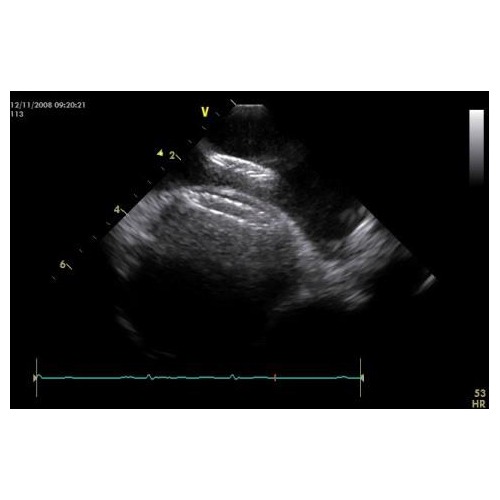

コンパクト型超音波診断装置、Vivid iqに搭載されるICEカテーテル(心腔内超音波カテーテル)機能。

ICEカテーテルの接続により、これまでの体表超音波検査に加え、デバイスによる治療、電気生理の分野にお役立

ていただけます。多々の医療器材により手狭になりがちなカテーテル検査室に、ノートタイプでコンパクトなVivid iqを活用いただけます。